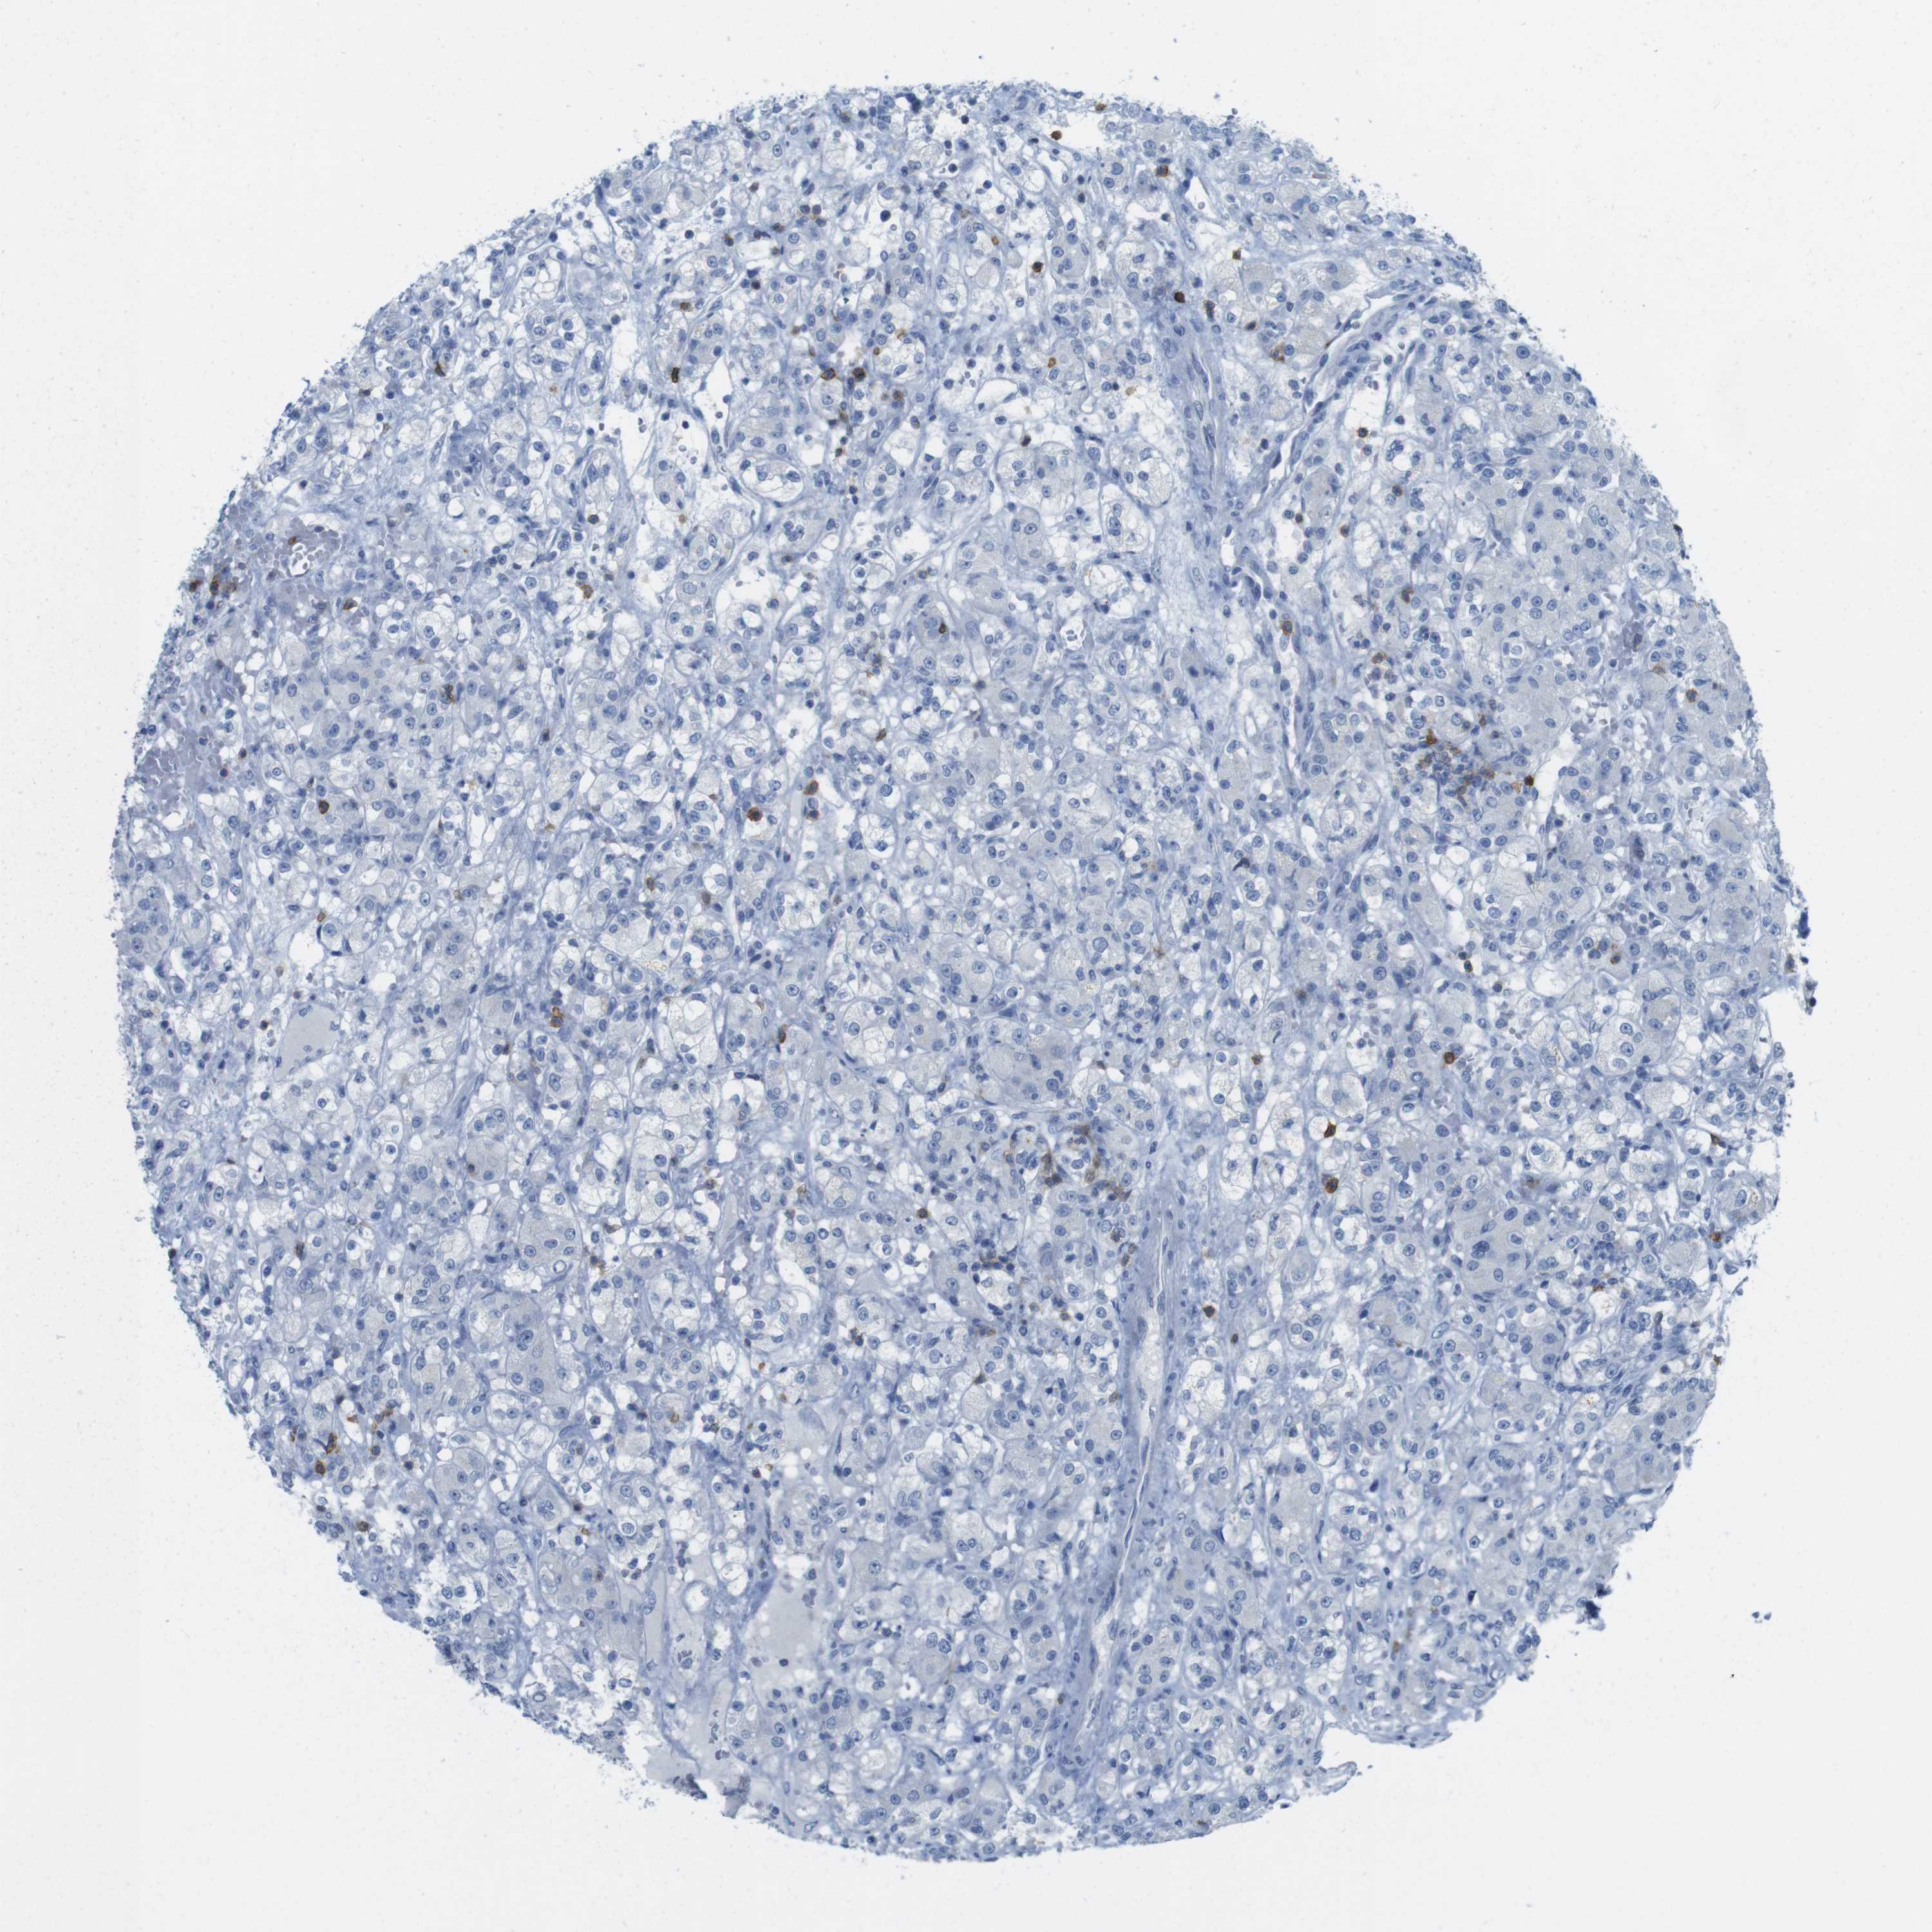

KIDNEY RENAL CLEAR CELL CARCINOMA (VALIDATION) - Interactive survival scatter ploti

The Survival Scatter plot shows the clinical status (i.e. dead or alive) for all individuals in the patient cohort, based on the same data that underlies the corresponding Kaplan-Meier plots. Patients that are alive at last time for follow-up are shown in blue and patients who have died during the study are shown in red.

The x-axis shows the expression levels (FPKM) of the investigated gene in the tumor tissue at the time of diagnosis. The y-axis shows the follow-up time after diagnosis (years). Both axes are complimented with kernel density curves demonstrating the data density over the axes. The top density plot shows the expression levels (FPKM) distribution among dead (red) and alive patients (blue). The right density plot shows the data density of the survived years of dead patients with high and low expression levels respectively, stratified using the cutoff indicated by the vertical dashed line through the Survival Scatter plot. This cutoff is automatically defined based on the FPKM cutoff that minimizes the p-score. The cutoff can be changed by dragging the vertical line or by entering a cutoff value in the square labeled "Current cut-off".

Under the Survival Scatter plot the p-score landscape (black curve; left axis) is shown together with dead median separation (red curve; right axis). Dead median separation is the difference in median mRNA expression between patients who have died with high and low expression, respectively. It is calculated as follows: median FPKM expression of dead patients with high expression - median FPKM expression of dead patients with low expression. This is intended to aid the user in visually exploring custom cutoffs and the associated p-scores and dead median separation.

Individual patient data is displayed and can be filtered by clicking on one or more of the category buttons on the top of the page. Categories describing expression level and patient information include: high, low, alive, dead, female, male and tumor stages. The scale of the x-axis can be toggled between linear and log-scale by clicking on the "x log" button. Mouse-over function shows TCGA ID, patient information and mRNA expression (FPKM) for each patient.

& Survival analysisi

Kaplan-Meier plots summarize results from analysis of correlation between mRNA expression level and patient survival. Patients were divided based on level of expression into one of the two groups "low" (under cut off) or "high" (over cut off). X-axis shows time for survival (years) and y-axis shows the probability of survival, where 1.0 corresponds to 100 percent.

CD5 is not prognostic in Kidney Renal Clear Cell Carcinoma (validation)

: 1.89

Average pTPM 4.7

Number of samples 100